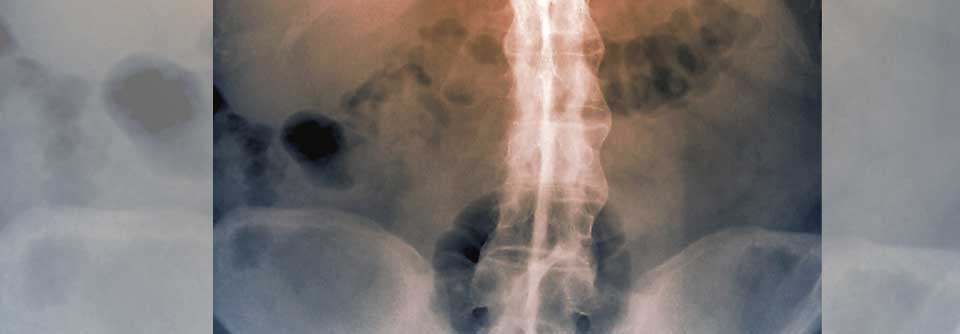

Bei Knirschen Bildgebung

Vorsicht, wenn Patienten mit rheumatoider Arthritis (RA) vermehrt über Knirschen im HWS-Bereich, Nacken- oder diffuse Kopfschmerzen berichten.